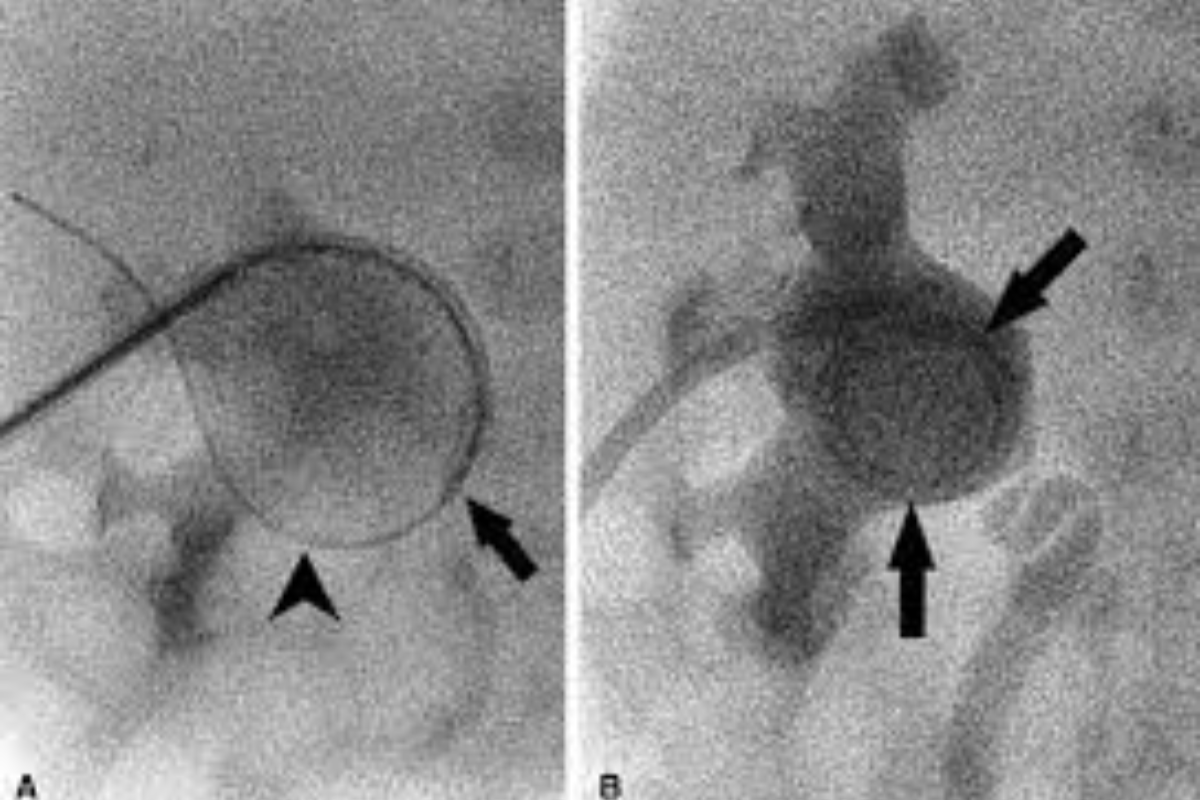

Interventional Radiology (IR) uses real-time imaging such as X-ray, ultrasound, CT, or MRI to guide tiny instruments through the body for treatment — without large surgical incisions.

Case's Video Gallery

Video Gallery